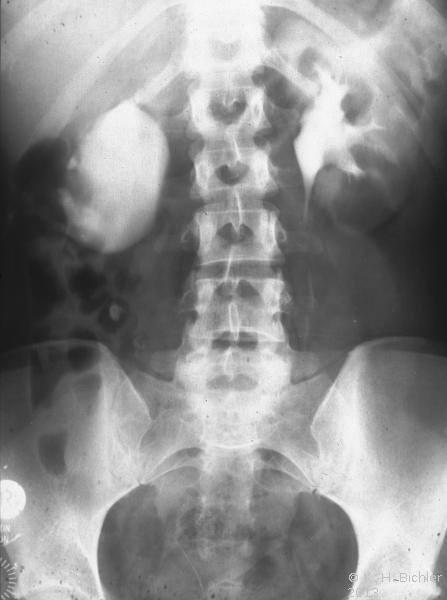

Rechtsseitige Ureterabgangsstenose mit deutlicher Hydronephrose. Behandlung mit Ureterabgangsplastik nach Anderson-Hynes (Abbildung 19).

• Abbildung 19:

2. Nach Ureterabgangsplastik